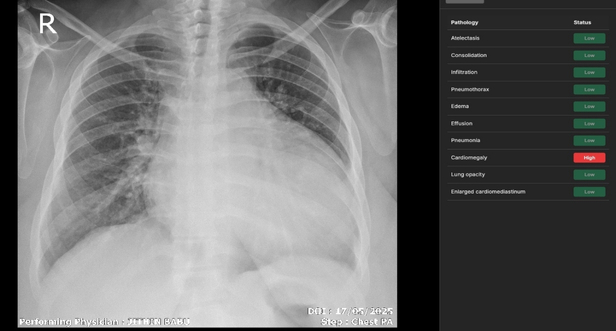

We provide high accuracy detection for 10+ chest pathologies. Our platform integrates seamlessly into your clinical workflow offering real time triaging and validated visual insights.

Our deep learning architecture is validated across 10+ critical pathologies, providing radiologists with a secondary set of eyes that never fatigues.

CARDIOMEGALY

View Detection

• Explainable AI: Visual heatmaps and clear rationale for every detection